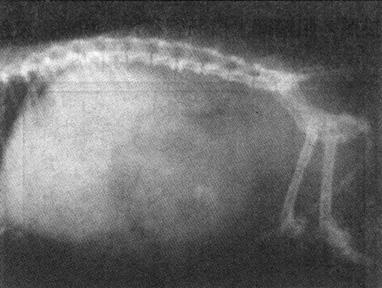

1)骨折 X线照片可显示黑色、透明的骨折线(纹),但只在X线平行通过骨的断裂面时,才能清楚显示出骨折线,故常规检查需拍摄包括上下两个关节在内的、两张互成90°角的前后(正位)位和侧位片。注意勿将骨骺线误为骨折线。确定骨折断端是否移位,以骨折近端为准,借以判断骨折远端的移位方向和程度(图1-1)。

图1-1 猫股骨远端骨骺分离

侧位显示股骨远端骨骺分离,并向后移位与股骨骨干成90°角